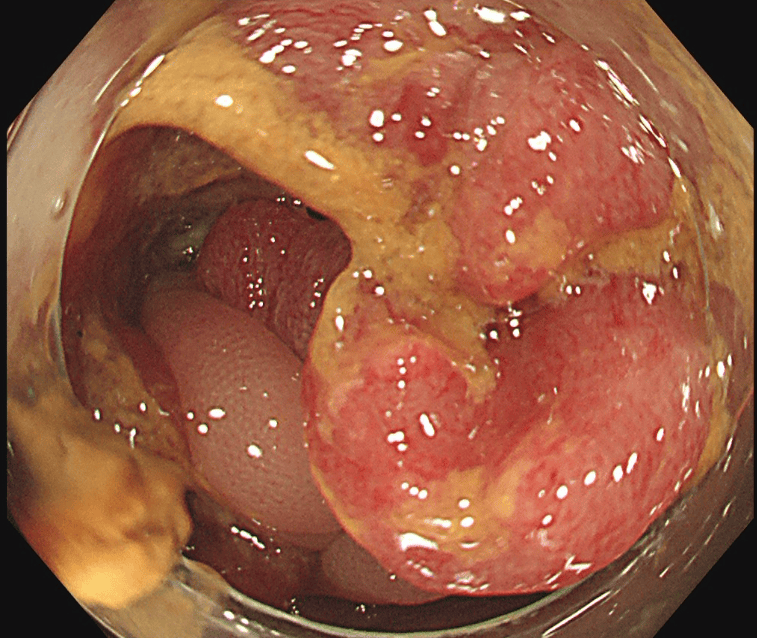

大腸がんに対してTNT療法を行った例

治療前

治療後